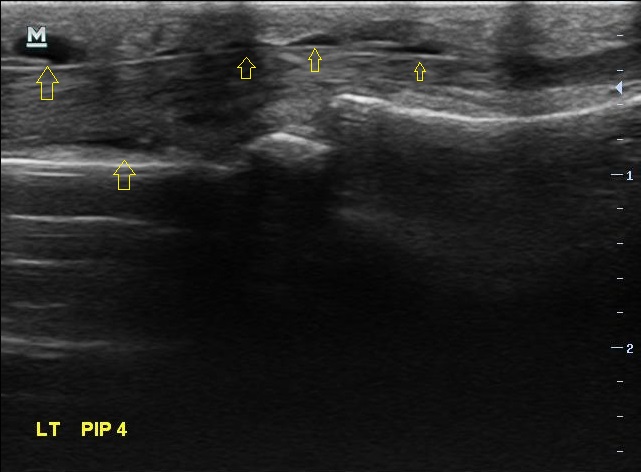

X-ray 검사상에는 특별한건 보이지 않습니다. 초음파 검사에서는.... 4번째 손가락을 굽혀주는 힘줄(4th flexor digitorum tendon)에 염증이 생겨있습니다.

2주 전보다 힘줄에 염증이 훨씬 심해져 있었습니다. 그리고

이번에는 한 부위만이 아니라 손가락 굽힘 힘줄을 따라 전체적으로 염증이 퍼져있습니다.